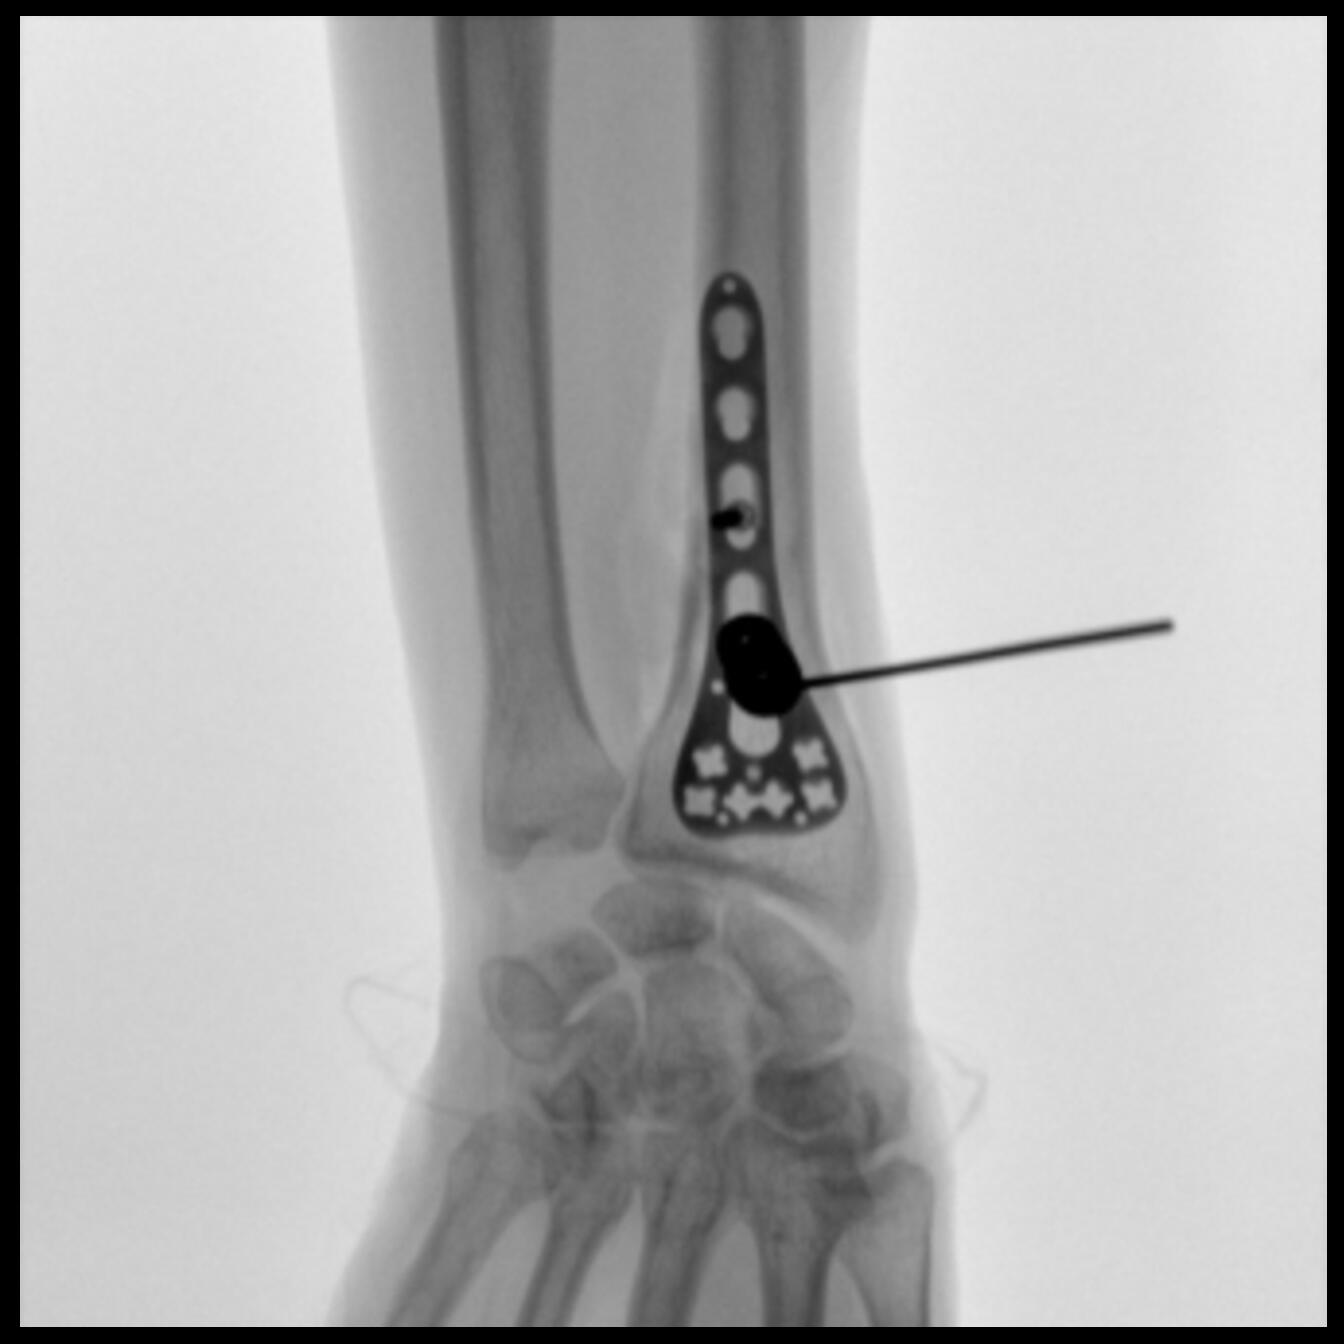

PLX118F-Plus配备了两种平板尺寸,大尺寸动态平板探测器成像面积较传统平板探测器提升了25%以上,在视野需求大的手术中,便于医生更好定位病灶点,规划手术方案,减少因视野范围不足而多次透视、点片造成的不便,不仅提高了手术效率,也减少了辐射剂量。